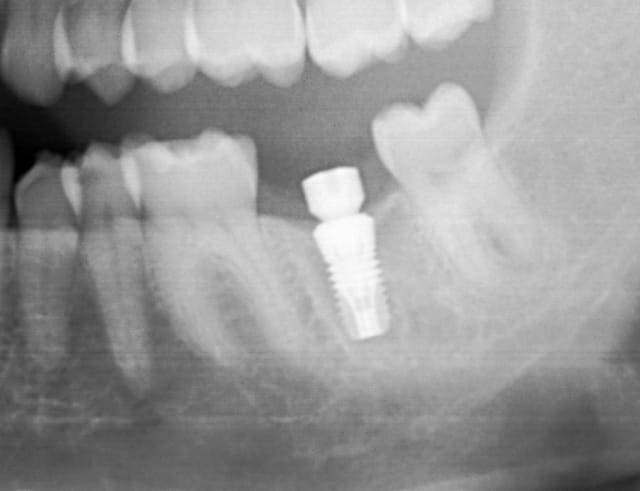

puisqu'il y a un post sur easyimplant, voici une modeste vue radiographique du premier que j'ai posé cette semaine (un 4.75 de diamètre (5.5 à la partie la plus large du col))

il s'agit de la même connectique que chez Astra et ce que je vois ici:http://www.klinik.uni-frankfurt.de/zzmk/werkstoffkunde/filme/Astra_Tech-Uebersicht-200N.avi

me conforte dans mon choix. Trousse simple et complète. C'est tout ce que je peux en dire pour l'instant.